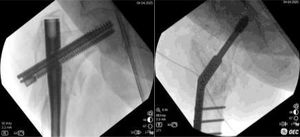

Good purchasing is verified by moving the construct under fluoroscopic vision (Fig. 7).

Over-valguization of the nonunionIn this moment, the DHS (of at least 6 holes) is introduced to the previously introduced cephalic screw. To correct the position of the femoral head, the plate should be placed just over the diaphyseal bone. To accomplish this, a Lowman retractor is recommended. Softly, the retractor is tightened, and the plate comes to the diaphyseal bone, reducing the nonunion (Fig. 6).

Final fixation and wound closingAfter plate gathering to the femoral shaft, get compression at nonunion site. It is quite important to avoid any distraction applied to the leg. Assure that no traction is given and compress slightly the limb. This is a very important point to assure proper compression and a buttress effect on the medial side of the nonunion. At this point, it maybe necessary to loosen a little bit the lowman retractor to facilitate compression.

Then, 3.5 cortical screws are applied. It is recommended that at least 6 bicortical screws with good purchase be inserted. If a longer plate is applied, the more distal screw can be a monocortical screw to diminish stress at the distal tip of the plate. If any screw is found not to hold properly, it may be useful to apply a wire cerclage over the plate.